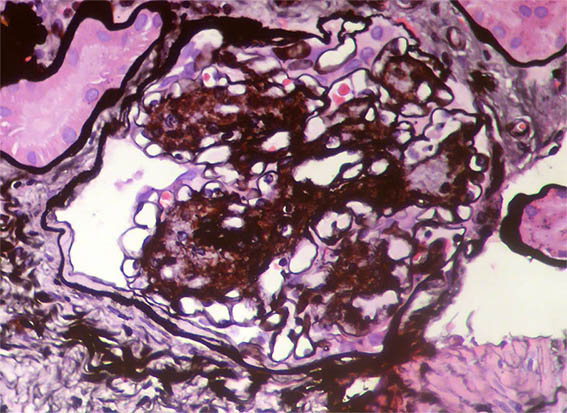

Figure 7. PAS, X400.

Figure 10. Methenamine-silver stain, X400.